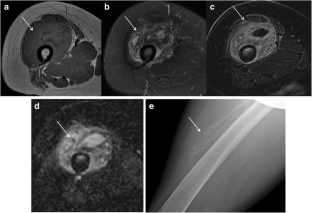

Fig. 1